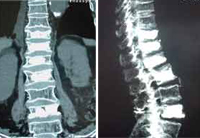

![]() Dr. Morgenstern while performing a Kyphoplasty |